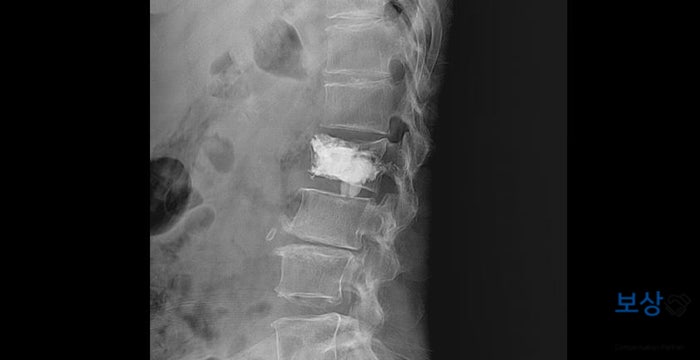

이처럼 뼈가 약한 경우에는 추가적인 골절 진행이 생길 가능성이 크기 때문에 시술적 치료가 불가피하였는데요. 골절된 척추체에 골 형성제(포스테오) 주입하여 굳히는 시술인 일명 **"골시멘트술(척추체 성형술)"**을 시행하게 되었습니다.

위 사진처럼 골 형성제(골시멘트)가 단단하게 굳으면서 안정적으로 척추를 지지해 줄 수 있는데요. 골시멘트술은 성공적으로 끝나게 되었고, 이후에는 허리보호기(TLSO) 착용하면서 약 2~3개월간 안정을 취하게 되셨습니다.